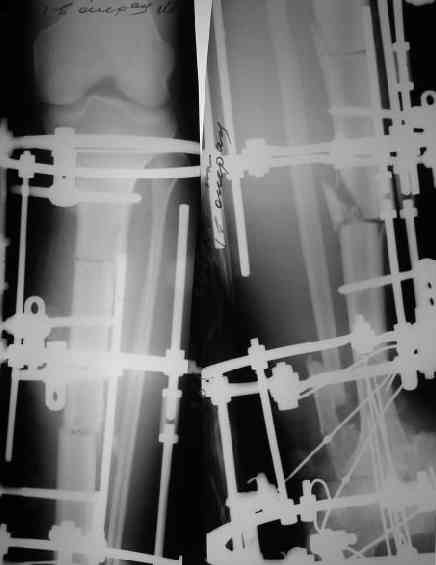

Решили не связываться с остеосинтезом, а сделать сразу берцово-пяточный блок. Снимки в приложении.

По завершении удлинения, наверно, заштифтуем.

Комментарии/критика приветствуются.